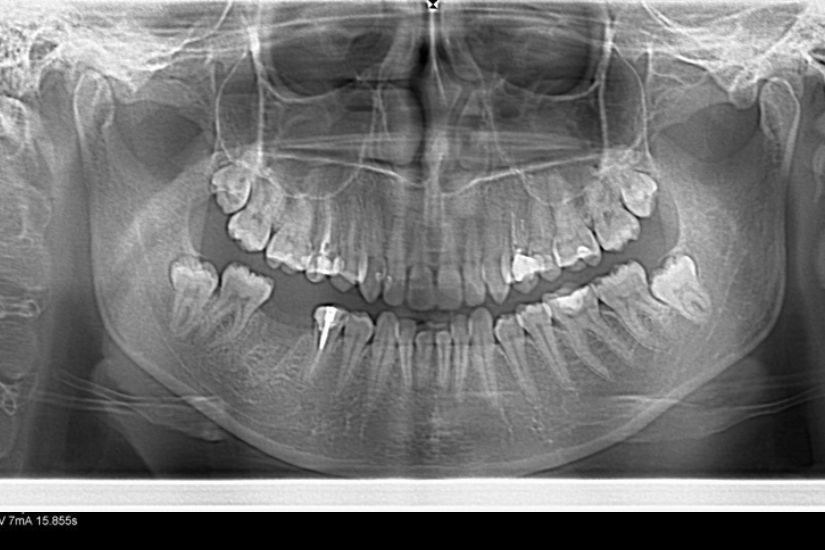

Dental Rehabilitation Using Alpha Dent Implant in Case of Reconstructed Mandible after Excision of Ossifying Fibroma

Dental Rehabilitation Using Alpha Dent Implant in Case of Reconstructed Mandible after Excision of Ossifying Fibroma Dr. Parit Ladani MDS